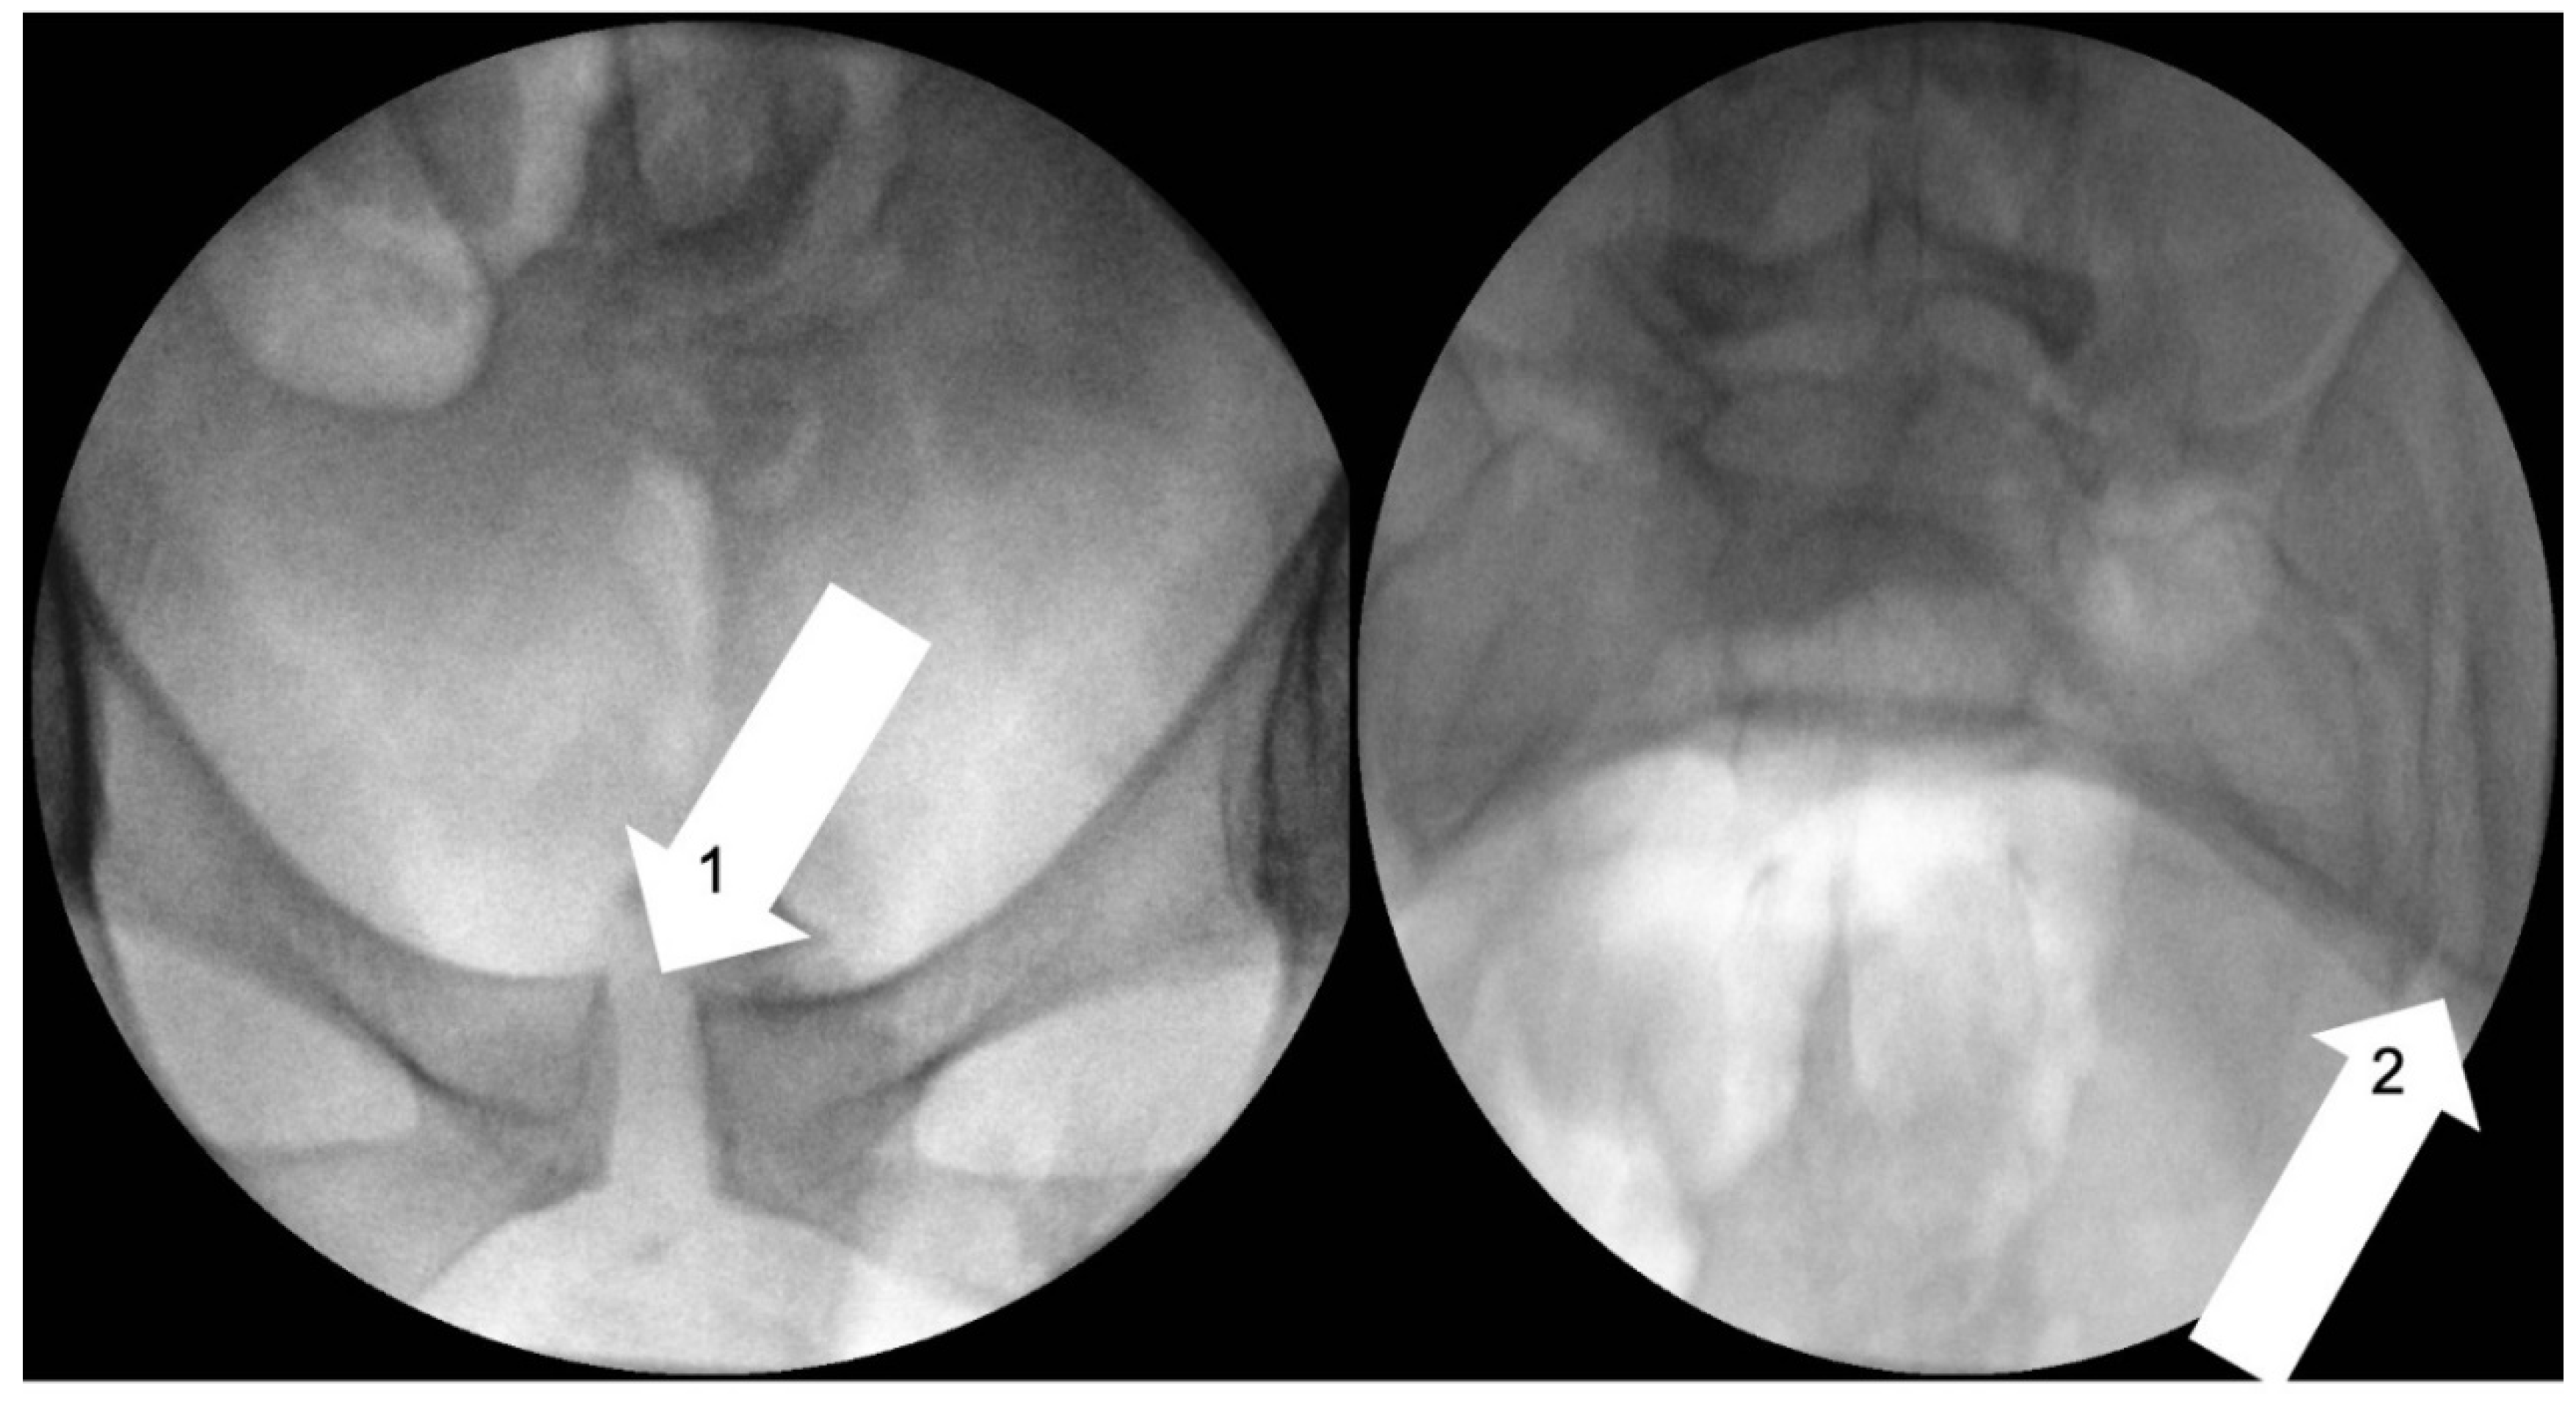

- Garras, D.N.; Carothers, J.T.; Olson, S.A. Single-leg-stance (flamingo) radiographs to assess pelvic instability: How much motion is normal? J. Bone Joint Surg. Am. 2008, 90, 2114–2118. [Google Scholar] [CrossRef] [PubMed]

- Björklund, K.; Bergström, S.; Nordström, M.-L.; Ulmsten, U. Symphyseal distention in relation to serum relaxin levels and pelvic pain in pregnancy. Acta Obstet. Gynecol. Scand. 2000, 79, 269–275. [Google Scholar] [CrossRef] [PubMed]

- Van Zwienen, C.M.; Van den Bosch, E.W.; Snijders, C.J.; Van Vugt, A.B. Triple pelvic ring fixation in patients with severe pregnancy-related low back and pelvic pain. Spine 2004, 29, 478–484. [Google Scholar] [CrossRef] [PubMed]